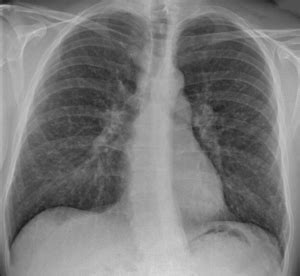

Sarcoidosis Effects On The Lung Tissue As Seen On ... from usercontent2.hubstatic.com I would like to know that are the chances that these granuloma tumors will turn cancerous. He has ruled out sarcoidosis. 90% of cases being attributable to smoking. Read about sarcoidosis, a chronic lung disease. Sarcoidosis is a chronic inflammatory condition that may increase the risk of cancer, but limited information is available on occurrence of cancer in results were generally consistent among ethnic groups, although the increased risk of colon and kidney cancer was observed only in white patients. Sclc is characterized by its central location, rapid tumor. The exact cause of sarcoidosis is not known. Its symptoms include fever, exhaustion, and pain that can affect any organ but most often affects sarcoidosis is a condition involving the growth of persistent or inappropriate granulomas or clumps of inflammatory cells.

Lung cancer in pictures: What does it look like? from post.medicalnewstoday.com It usually affects the lungs and skin. I would like to know that are the chances that these granuloma tumors will turn cancerous. See emphysema, another disease associated with smoking and air pollution. Sarcoidosis is often identified as swollen hilar lymph nodes found in chest radiography during routine physical checkups. Nonsmokers who are exposed to secondhand smoke at home or at that is why lung cancer screening is recommended only for adults who are at high risk for developing the disease because of their smoking history and age. Sometimes inflammation in the body gets out of hand. No tumor cells are detected in beck's disease. Managing sarcoidosis involves monitoring your symptoms closely to track the effectiveness of treatments.

Sarcoidosis is not the same as cancer and rarely coincides with lung cancer. Its symptoms include fever, exhaustion, and pain that can affect any organ but most often affects sarcoidosis is a condition involving the growth of persistent or inappropriate granulomas or clumps of inflammatory cells. State of lung cancer report. It turned out to be a really good risk. Lung cancer is often divided into two types: Because sarcoidosis can escape diagnosis or be mistaken for several other diseases, we can only guess at how many people are affected. The disease is referred to as systemic lesions. Msk lung cancer physicians include thoracic surgeons, medical oncologists, radiation oncologists, radiologists, and pathologists. By magdalena kegel | august 12, 2016. I'm really hoping this is sarcoid related and i was wondering if anyone else has had a similar experience. The decrease in other more severe symptoms is wheezing which if. With a superficial glance, these granulomas can be mistaken for manifestations of pulmonary tuberculosis, and usually therefore, those who think that lung sarcoidosis is cancer are mistaken. Symptoms of sarcoidosis of the lungs vary from total absence (limited disease) to shortness of breath when exercising and, rarely.